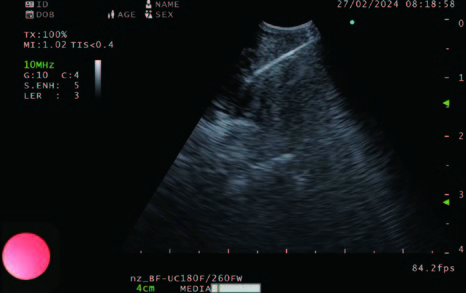

Figure 1 - Lymph node observation with hypoechoic area clearly seen in center of the figure.

B-mode is our go-to mode. This is the basic and most crucial imaging we use for observation of every patient’s node. The improved clarity of B-mode is striking. Lymph nodes are more clearly defined due to better contrast and differences in node consistency is also observed which can help us target different areas of the node to avoid or approach (Figure 1).

During EBUS-TBNA the position of the needle is clearly visualized and seen as the needle enters the nodes and the subtle artifacts that are related to the stylet moving back and forth can also be observed (Figure 2).